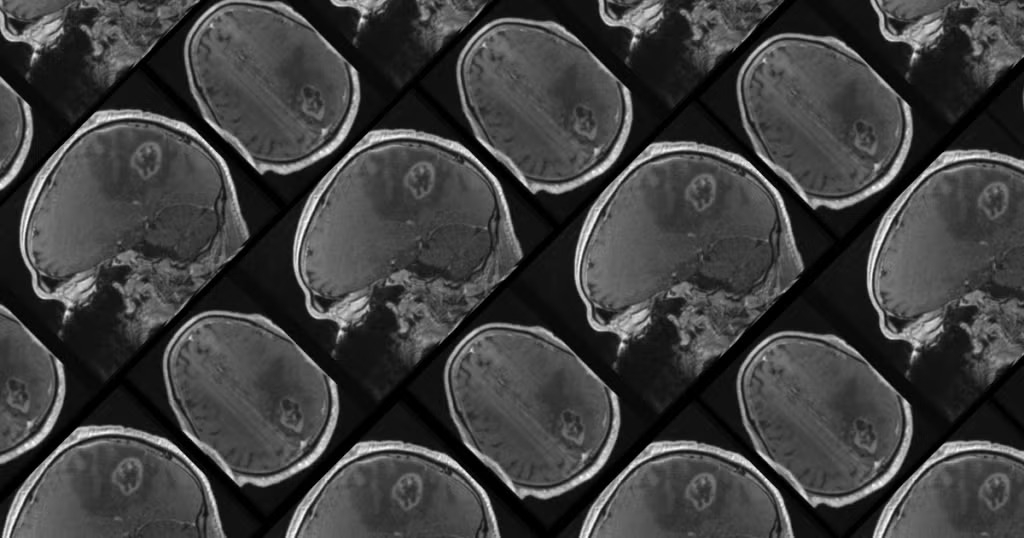

Nobel mükafatı laureatı və biokimyaçı, ABŞ-nin Şimali Karolina Universitetinin (UNC) professoru, tibb elmləri doktoru Aziz Sancarın rəhbərlik etdiyi tədqiqat qrupu beyin xərçənginin aqressiv və ölümcül bir forması olan qlioblastomanın müalicəsində inqilab edə bilər.

Glioblastoma beyin xərçənginin sürətlə böyüyən və ölümcül bir formasıdır. Bu gün xəstələrin yalnız ~7%-i diaqnoz qoyulduqdan sonra beş ildən çox yaşayır. Və aqressiv xərçənglə bağlı çoxlu tədqiqatlara baxmayaraq, qlioblastomanın müalicə üsulları son 20 ildə eyni səviyyədə qalıb.